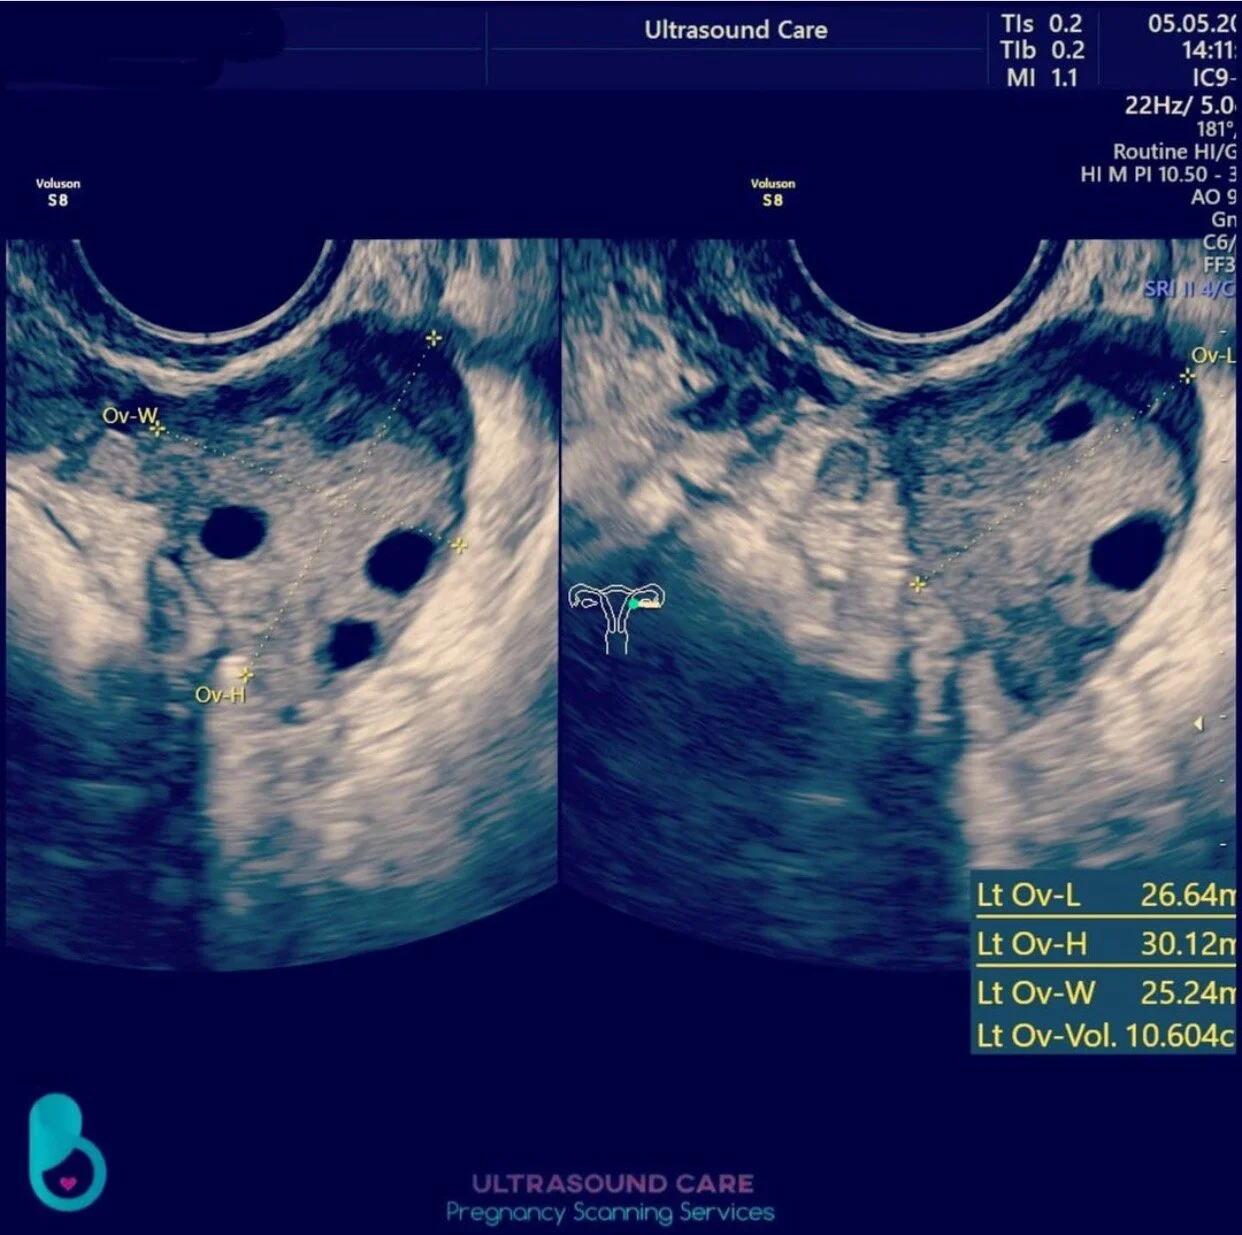

Gynae (Pelvic) Scan

Gynae (Pelvic) scans are essential for assessing overall reproductive health. At Ultrasound Elite, we provide high-quality Gynae/Pelvic scans for those seeking thorough and accurate examinations. Whether you need an endometrial lining measurement, a follicular count before IVF, or an assessment for concerns such as irregular periods, ovarian cysts, or fibroids, our expert team is here to support you.